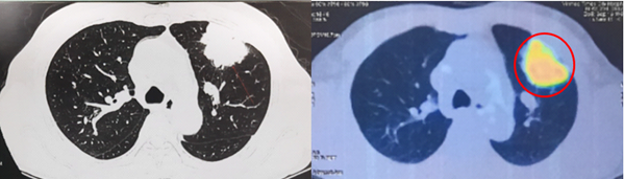

PET/CT toàn thân với 18FDG:

Hình 6: Hình ảnh khối tăng chuyển hóa FDG ở thùy trên phổi trái tương ứng với tổn thương nguyên phát đã biết (vòng tròn đỏ) (cT3).

Hình 7: Chưa phát hiện hạch to, tăng chuyển hóa FDG khu trú bất thường ở trung thất - hố thượng đòn, rốn phổi 2 bên (cN0).